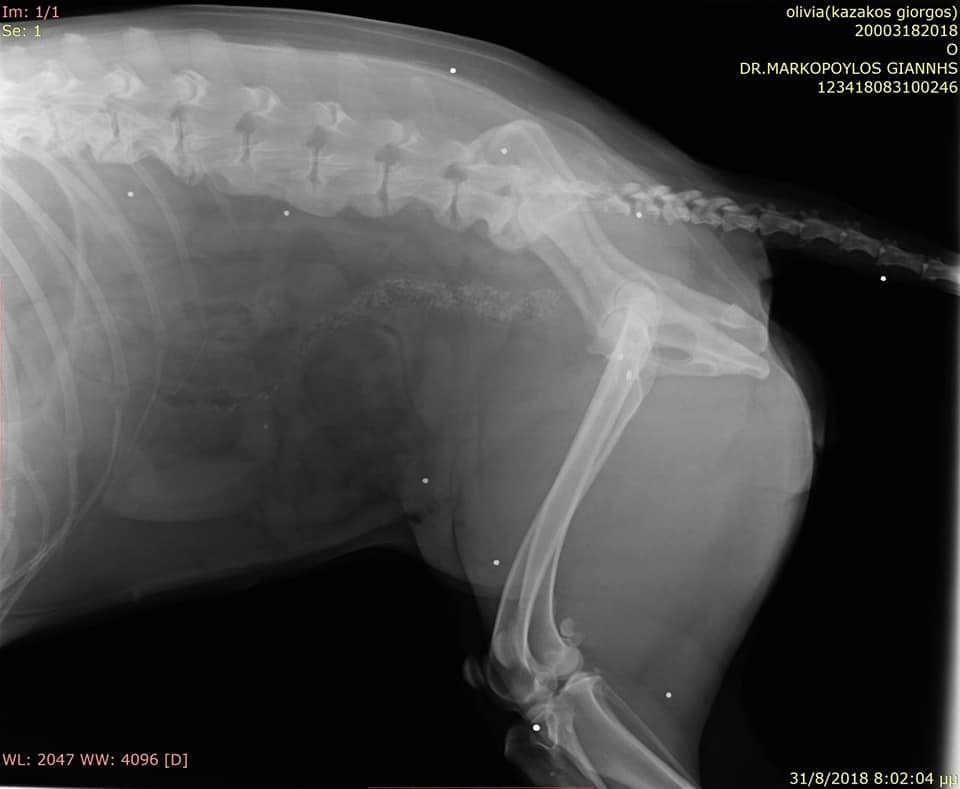

Στο κτηνιατρείο του Γιάννη Μαρκόπουλου στην Κυπαρισσία μεταφέρθηκε στις 31 Αυγούστου ο σκύλος, ο οποίος πυροβολήθηκε με καραμπίνα στα Φιλιατρά Μεσσηνίας από κάτοικο της περιοχής.

FiliatraMessiniasPyrovolimenosSkylosAktinografia 1Η ακτινογραφία έδειξε τα σκάγια στο σώμα του σκύλου.